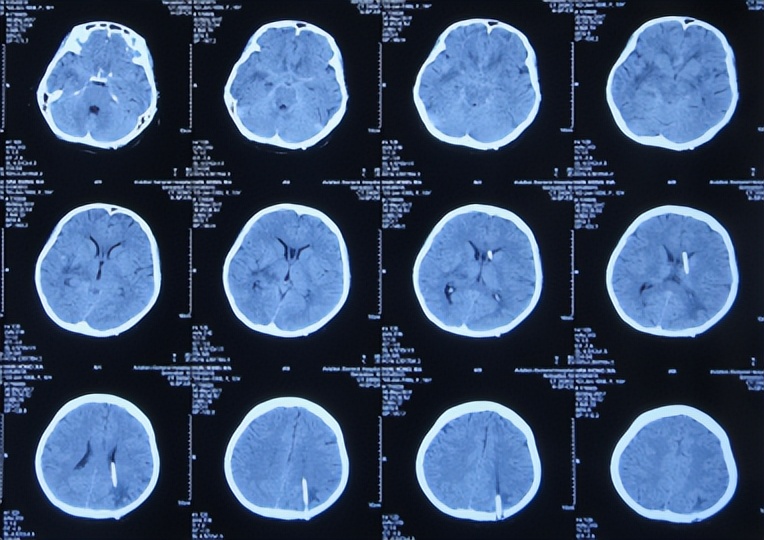

入院治疗3天后即2017年4月5日(发病后16天后),脑CT( 图-3 )后继续给予相关治疗。

图-3: 2017年4月5日脑CT